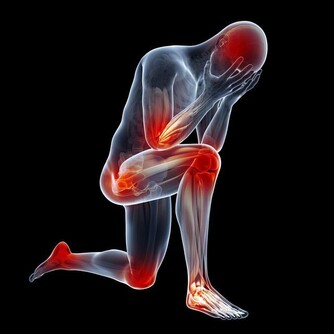

骨科醫生不希望你:總是坐軟沙發

沙髮質地太軟,人坐上去,腰椎缺乏足夠支撐,容易骨盆向後傾斜。

久而久之會導致腰部肌肉勞損、骨質增生,甚至誘發腰椎間盤突出。

最好坐有靠背的硬椅子,臀部充分接觸椅面,腰背部貼緊椅背,使腰背部肌肉更放鬆,腰椎間盤壓力也較小。